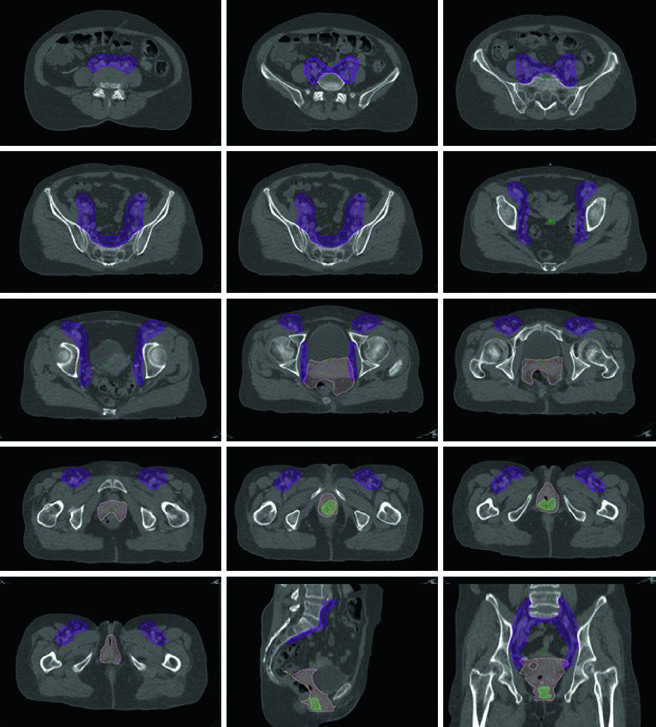

Definição de volumes segundo o protocolo NRG-GY006

| Volume | Definição |

|---|---|

| GTV | Toda doença macroscópica visível, avaliada por informação clínica, exame físico, estudos radiográficos, exame endoscópico e biópsias |

| CTV1 | GTV + cérvice + útero |

| CTV2 | Paramétrios e terço superior da vagina (ou metade superior se vagina clinicamente envolvida) |

| CTV3 | Linfonodos ilíacos comuns, ilíacos externos, ilíacos internos e pré-sacrais. Borda superior na bifurcação aórtica (≈ L4–L5). Pré-sacrais até S2–S3. Ilíacos externos até o topo das cabeças femorais. Margem de 7 mm ao redor dos vasos, excluindo osso, músculo e intestino |

| CTV_boost | Linfonodos pélvicos macroscópicos; inclui paramétrio se boost parametrial indicado |

| ITV | CTV1 delineado em TC com bexiga cheia e vazia, combinados |

| PTV1 | CTV1 + 15 mm de expansão uniforme |

| PTV2 | CTV2 + 10 mm de expansão uniforme |

| PTV3 | CTV3 + 5 mm de expansão uniforme |

| PTV4 | ITV + 7 mm de expansão uniforme |

| PTV_boost | CTV_boost + 5 mm de expansão uniforme |

Fonte: Target Volume Delineation and Field Setup, 2nd Edition (Table 21.1, protocolo NRG-GY006)

Se linfonodos para-aórticos estiverem envolvidos, deve-se empregar técnica de campo estendido, estendendo a borda cranial do CTV superiormente até o interespaço L1/L2 ou 3 cm cranial ao linfonodo mais superior envolvido. Os PTVs são criados para cada CTV e o PTV final é a combinação de todos. Expansões diferenciais CTV-PTV são utilizadas para cada componente baseadas no grau de movimento orgânico interno e incerteza de posicionamento.

O delineamento é similar à RT pélvica para câncer cervical. O GTV inclui toda doença macroscópica. O CTV se divide em CTV1 (GTV + útero inteiro), CTV2 (tecidos paravaginais/parametriais + 3 cm da vagina proximal) e CTV3 (igual ao cenário pós-operatório). Se a vagina distal (terço inferior) estiver envolvida, linfonodos inguinais devem ser contornados continuamente dos ilíacos externos até 2 cm caudal à junção safeno-femoral. Com envolvimento para-aórtico, campo estendido similar ao da Tabela 21.1. Expansões diferenciais: PTV1 = 15 mm, PTV2 = 7–10 mm, PTV3 = 5–7 mm. Boost adicional de 5–15 Gy pode ser adicionado para doença nodal macroscópica ou envolvimento parametrial, com SIB ou abordagem sequencial.